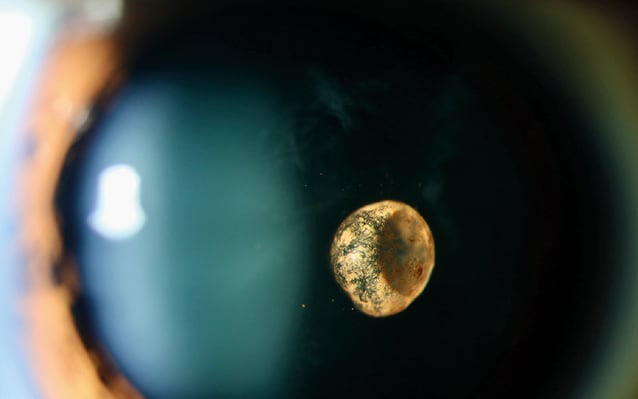

The eye is a source of inspiration, both artistic and scientific. But irrespective of the instrument used, the structures examined, or whether the images are depicted by paintbrush, photography or precision instrument, beauty abounds.